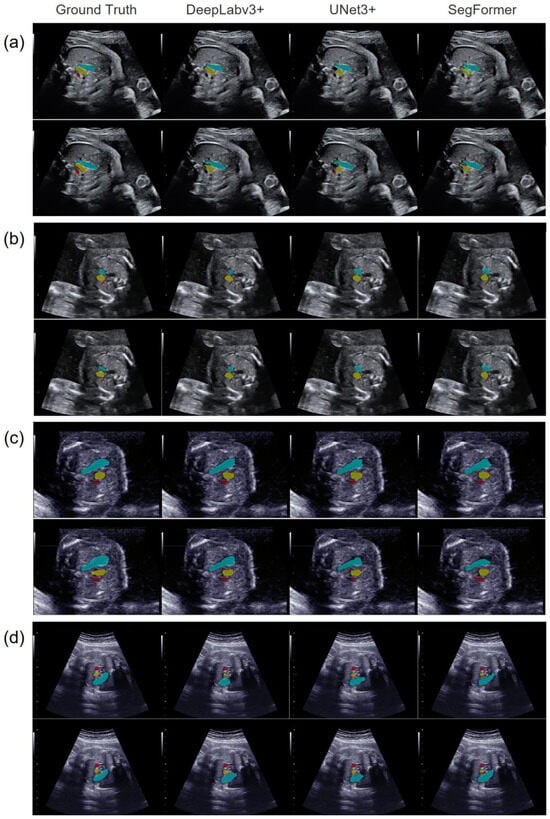

3.1. Evaluation of Vascular Segmentation